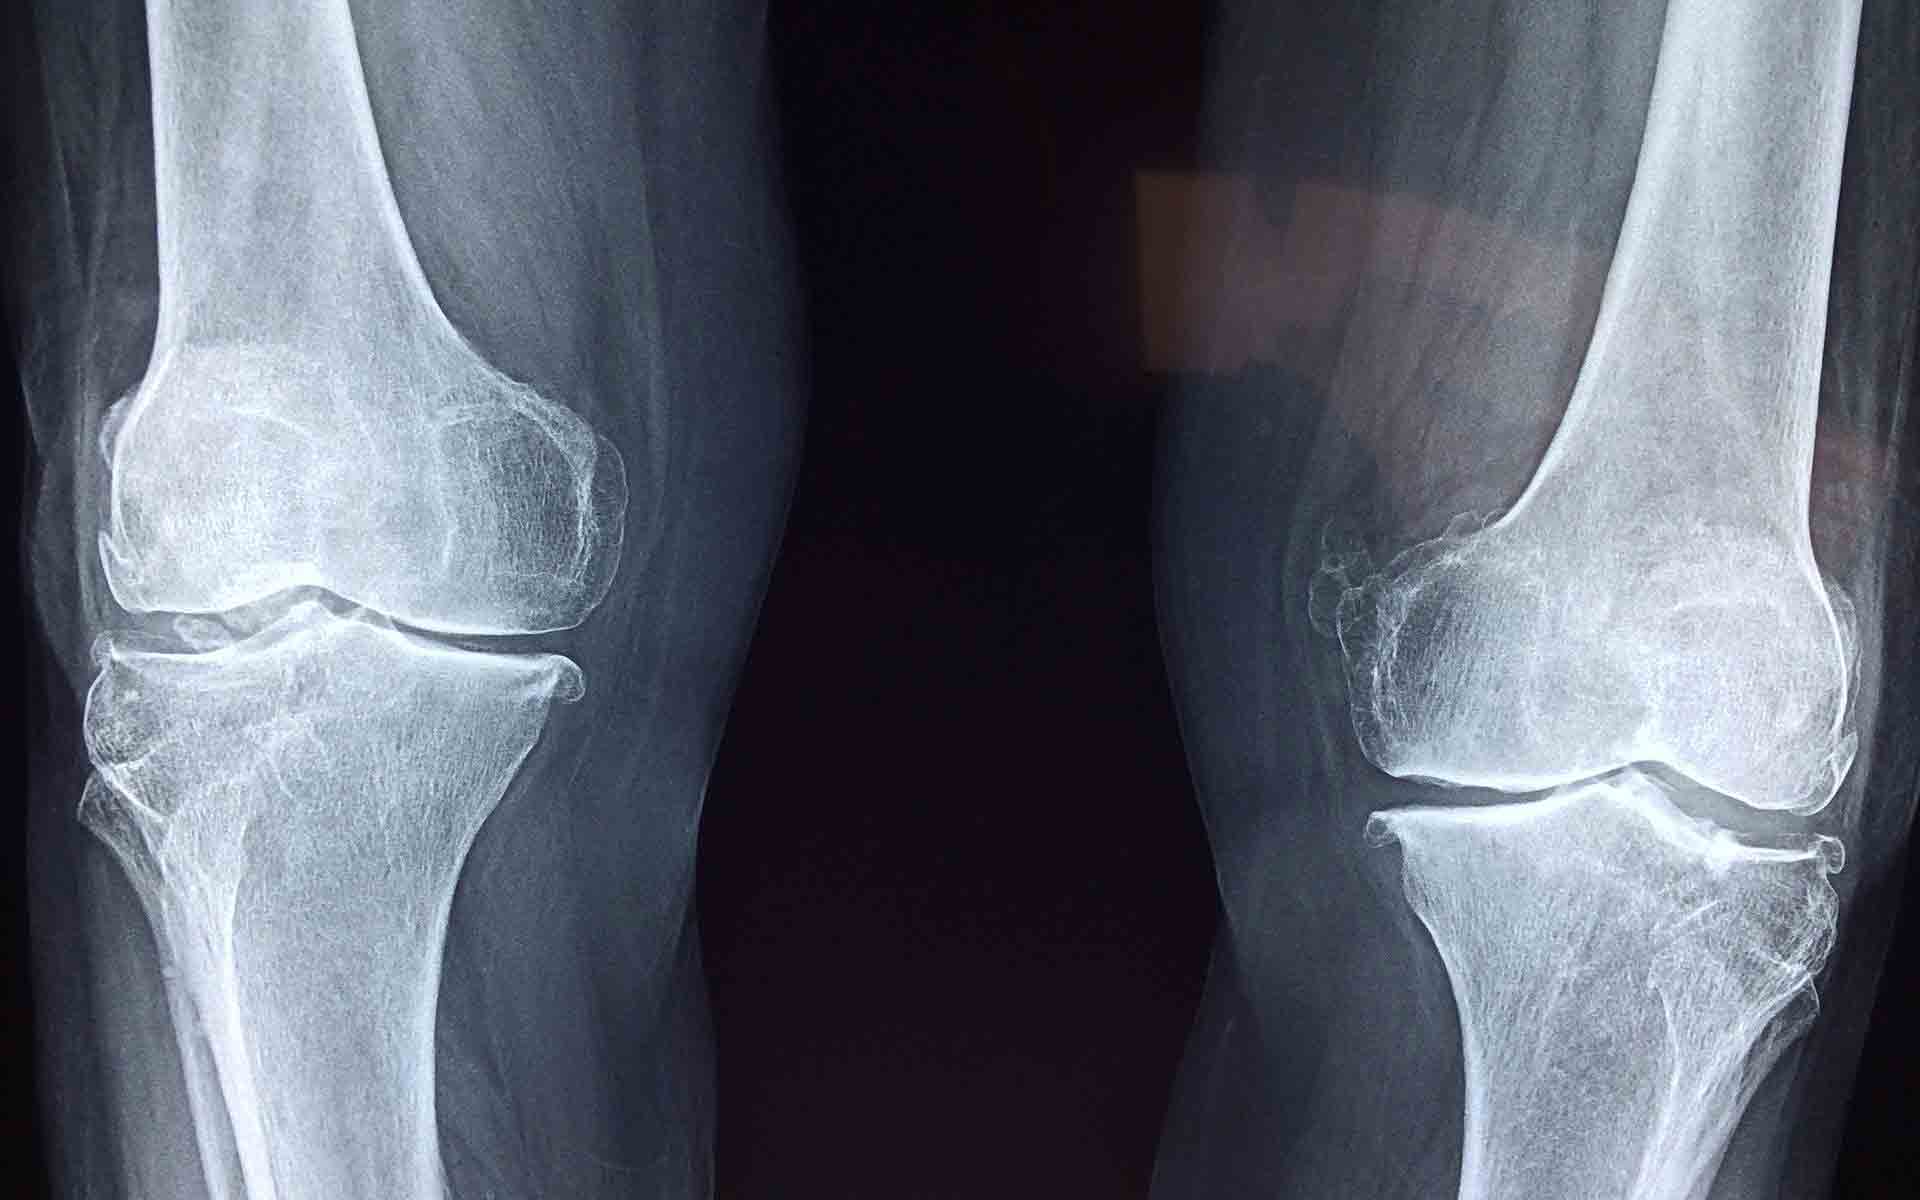

Diagnóstico por imagen. El diagnóstico por imagen médica, tales como una radiografía o una resonancia magnética, permite la visualización de las estructuras anatómicas dentro de la rodilla, con el fin de medir la gravedad de la lesión del ligamento. El diagnóstico por imagen también ayuda a determinar si otras estructuras de la rodilla han sido dañadas. Por ejemplo, un paciente puede tener un esguince de rodilla, así como una fractura de hueso o un desgarro de menisco.

Los rayos x ayudan a un diagnóstico de una fractura de hueso, y una resonancia magnética permite la visualización de lesiones en tejidos blandos, como tendones o ligamentos.